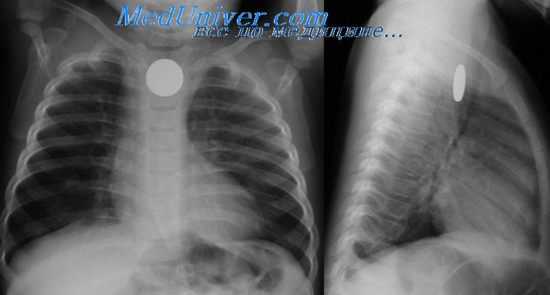

Эзофагография при атрезии пищевода